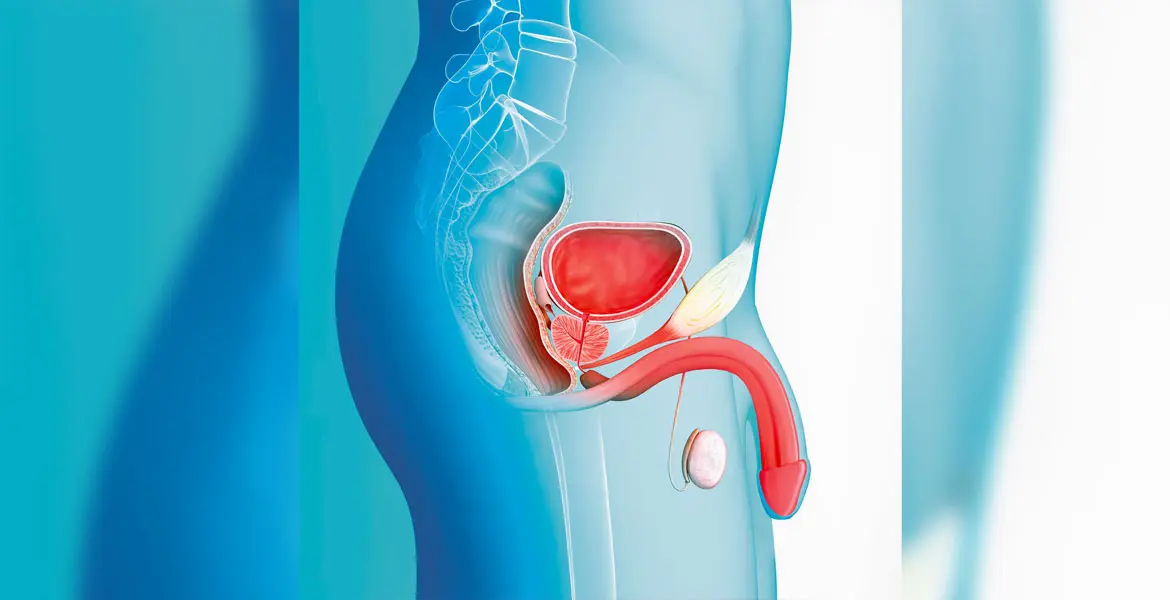

ما هو ضعف الانتصاب؟

ضعف الانتصاب هو عدم قدرة الرجل على الوصول إلى انتصاب كافٍ أو المحافظة عليه لفترة تسمح بإتمام العلاقة الحميمة بشكل مُرضٍ.

قد يحدث بشكل مؤقت بسبب التعب أو القلق، وقد يكون مزمنًا عندما يتكرر باستمرار.